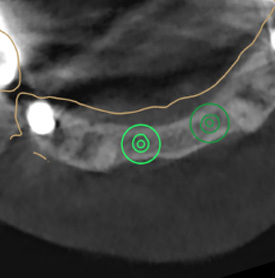

CBCT